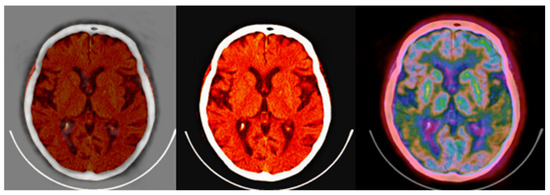

3.1. CIT Application

3.2. Colormap Folding Application